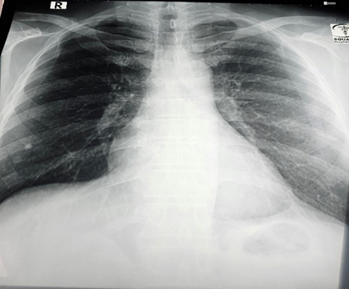

Cardiac enzymes were normal. All biochemical investigations were within normal limit. Chest x-ray P/A view shows normal findings.

Figure 2: X-ray Chest P/A view showing normal findings.